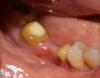

На днях сменила коронки, так как за 10 лет немного оголились корни. Мост (7-й и 5-й, между ними 6-ка нет зуба) В первое посещение мне изготовили временные коронки из акрила( который применяют в ногтевом сервисе при наращивании ногтей) обработали и обточили зубы покрыли их каким то составом и надели временный мост. К вечеру сошла анестезия и ужасно заболели зубы под мостами, с 2-х сторон. Я сняла их и увидела, что на десне между подточенными зубами ранка покрытая белым налетом ( гной наверное) смотрите фото. Врач объяснил, что это аллергия на акрил, и что произошел ожег. Тем временем изготовили металлокерамические коронки, и я попросила, чтобы мне не закрывали полностью зубом пораженную десну а оставили промывное пространство. Постоянные коронки мне закрепили на временную фиксацию. С одной стороны коронка села нормально, с другой, живые зубы побаливают, вместе с десной пораженной. Ощущения, что прикус высоковат, при смыкании боль немного усиливается. Но понять отчего сложно, то ли от десны то ли от зубов. Боль общая. На одном зубе припухла немного десна под коронкой.

По Вашему фото сложно понять, где белая ранка. Не резкое фото. Лучше к специалисту, потому что для диагностики, ещё необходимо "потрогать-пощупать", постукать, глубину карманов прозондировать, провести температурные пробы, снимок сделать.